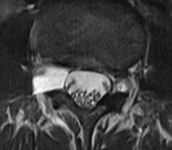

Resim 2. Sagittal ve aksiyal T2 ağırlıklı inceleme.

L3-4 seviyesinde sağ nöral foramen yerleşimli lezyon, tüm sekanslarda BOS intansitesine eş dansitede olmasına binaen bir perinöral kist olarak değerlendirildi. Bu lezyonun komşu kökü basarak semptomatik olabileceği, ancak bu yerleşimdeki bir kistin hastadaki gibi bel ve sol bacak ağrısından çok, sağ bacak ağrısı ve sağ L3 kök bulguları yapmasının bekleneceği düşünüldü. Bel ve sol bacak ağrısının L5-S1 seviyesindeki ılımlı disk dejenerasyonuna bağlı olabileceği öngörüldü. Sağ bacakta radiküler bir ağrı olmadıkça perinöral kiste yönelik radyolojik takibe gerek görülmedi.